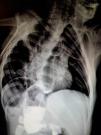

A 9-year-old boy was diagnosed with a tracheoesophageal fistula and esophageal atresia at birth, both of which were surgically repaired. At the follow-up visit with the services of Pediatrics and Gastroenterology of our hospital center, the chest and abdominal x-ray presented herein showed the presence of situs inversus, morphologic abnormalities, and vertebral fusion, as well as postsurgical changes in the esophageal repair, all of which are characteristic findings of the VACTERL association (Fig. 1).